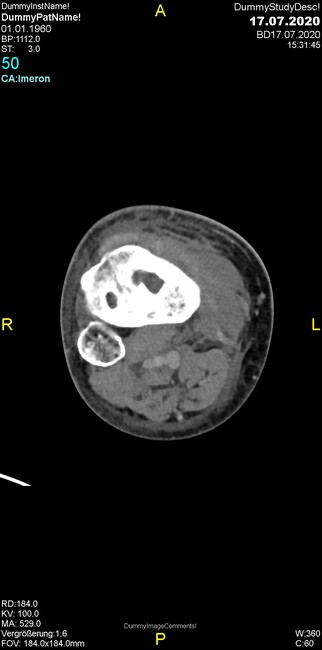

Um welche Modalitäten handelt es sich?

- Röntgen p.a. und lateral, CT coronar Knochenfenster, CT axial Weichgewebsfenster

- Röntgen p.a. und oblique, CT coronar Knochenfenster, CT axial Weichgewebsfenster

- Röntgen p.a. und lateral, CT sagittal Weichgewebsfenster, CT coronar Knochenfenster

- Röntgen p.a. und oblique, CT sagittal Knochenfenster, CT coronar Weichgewebsfenster

- Röntgen p.a. und lateral, CT coronar Weichgewebsfenster, MR axial

Was fällt in der CT im Knochenfenster auf?

- Mediale Gelenkspaltverschmälerung

- Dezente Erosion der fibulären Kortikalis

- Frakturspalt der lateralen Tibiametaphyse

- Weichgewebskalzifikationen lateral angrenzend an den Gelenkspalt

- Osteolyse der Tibiametaphyse unter Beteiligung der Kortikalis

Was kommt differentialdiagnostisch in Frage?

- Kompartmentsyndrom

- Osteomyelitis mit Weichgewebsanteil

- Metastase mit pathologischer Fraktur

- Rheumatoide Athritis

- Posttraumatische Verletzung